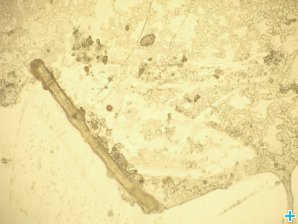

Optical micrograph (reflection microscopy) of an EBC sample of a worker, containing particles Optical micrograph (reflection microscopy) of an EBC sample of a worker, containing particles Courtesy of IST/ITN

EBC sample of a worker